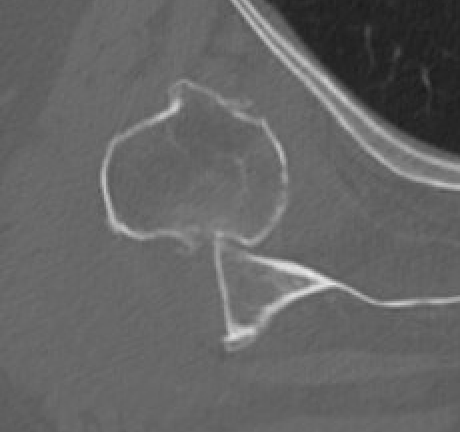

CT

Assess bone stock / glenoid bone loss / Hill Sachs lesions

Chronic shoulder dislocation with large Hill Sachs and minimal glenoid deficiency